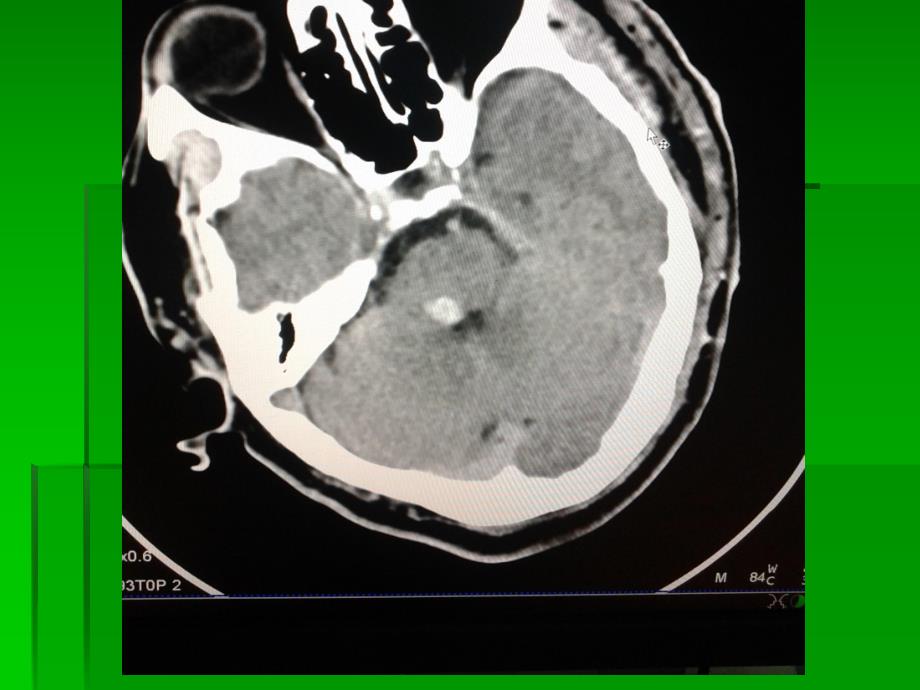

海绵状血管瘤为红色圆形或分叶状血管团,形似草莓或桑葚,切面如海绵状